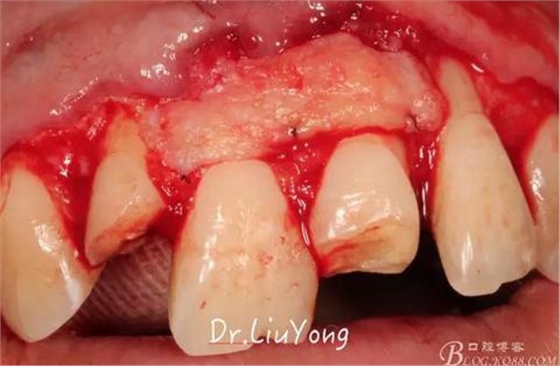

A區(qū)腭側所移取的上皮下結締組織瓣,如上圖